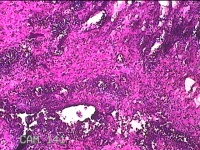

性别

男

年龄

51岁

临床诊断

躯干皮脂腺囊肿

一般病史

发现腰背部结节20余年,伴近日局部隐痛不适及少许渗出。

标本名称

腰背部结节

大体所见

灰白暗红色结节1.8x0.5x0.3cm一个,表面糜烂,切面灰白暗红色,质软。

图2